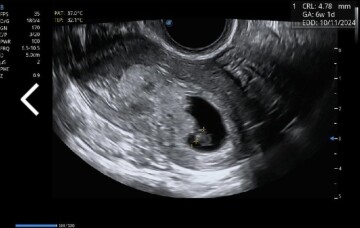

Dobrý denKolik dní to je podle velikosti reálné po ovulaci?Děkuji

Dobrý den,

jedná se o velmi časnou fázi těhotenství, přesně stáří Vám takto nelze říct, nicméně vzhledově embryo odpovídá cca 6.-7. gestačnímu týdnu.